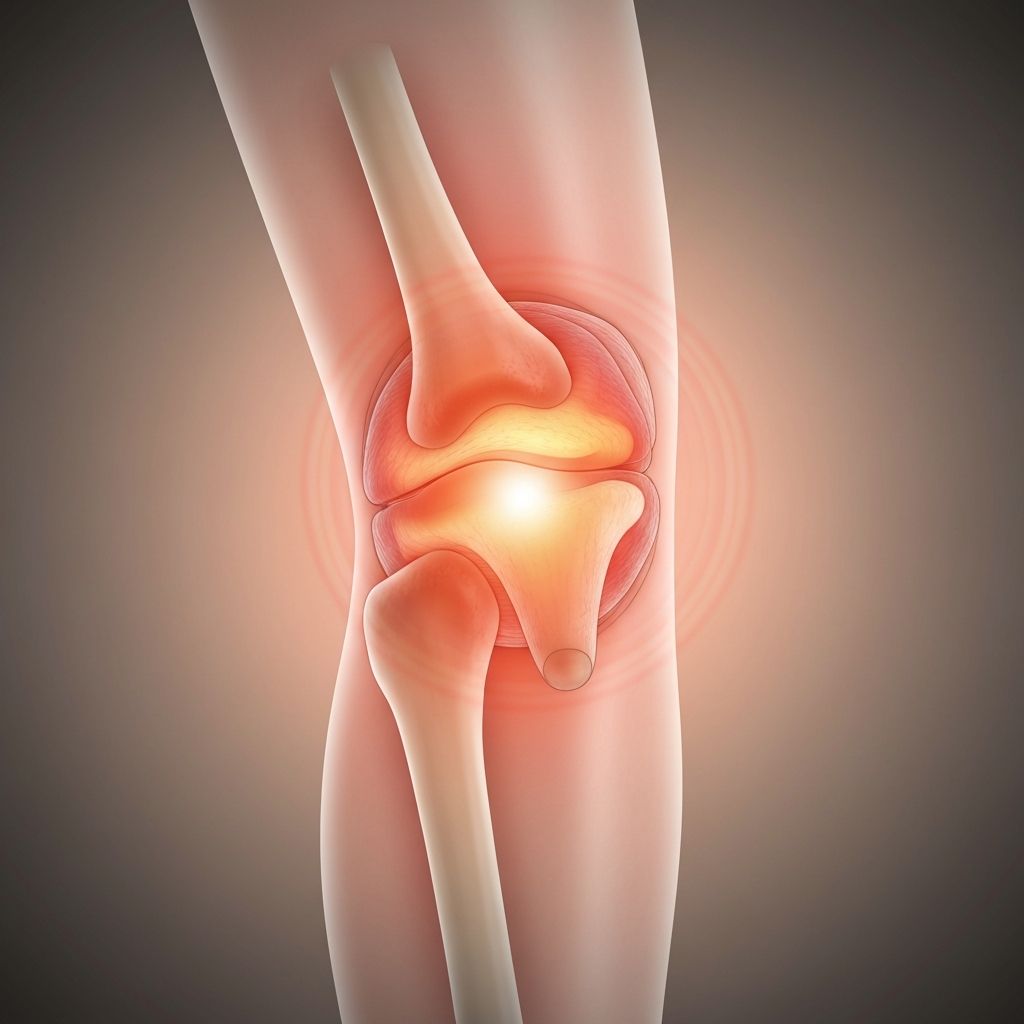

Knee Problems

Common knee conditions including meniscus tears, ligament injuries, and arthritis.

Details

Symptoms: Knee pain, swelling, clicking sounds, instability, locking, difficulty climbing stairs

Treatments: Conservative management, arthroscopy, ligament reconstruction, partial or total knee replacement

Prevention: Maintain healthy weight, strengthen thigh muscles, low-impact exercises, proper footwear